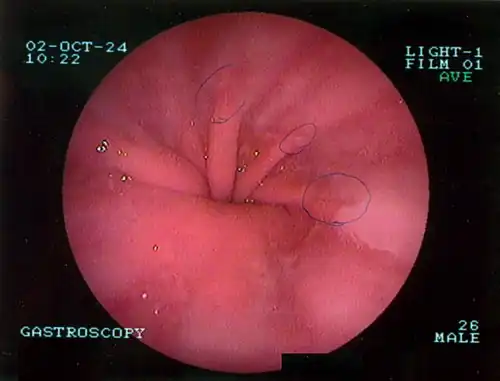

Upper GI endoscopy depicting hiatal hernia

Upper GI endoscopy in retroflexion showing Type I hiatal hernia